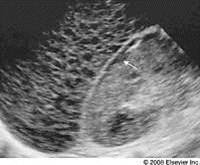

Cirrhosis

parachyma degernerates and lobes infiltate with fat

most common cause ALCHOL

SYM: nauses weight loss flatulence varicosities

SONO

Not advanced: hyperechoic, enlargment, decreased vasculature

ENd stage small noduar, ascites suround